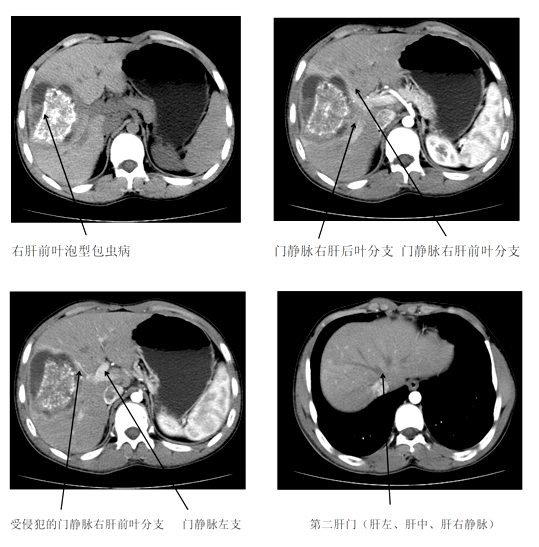

2019年3月底,一位来自壤塘县年仅17岁的男性患者,因腹部不适2月前来州人民医院就诊,经医生细致查体和术前检查诊断为右肝前叶泡包虫病(P2N0M0)。

州人民医院外二科喻定刚主任医师在认真阅读术前CT片后,考虑患者门静脉右前叶分支受侵犯,无法保留,为减少术后并发症,拟定行解剖性右前肝叶切除术,即精准解剖性Ⅴ+Ⅷ段切除术。2019年03月26日,经过充分的术前准备,由喻定刚主任医师主刀、罗斯满副主任医师和陈见中主治医师共同为患者在全麻下进行了解剖性肝Ⅴ段、Ⅷ段切除术,手术顺利,全程手术时间约4小时,患者在术中出血仅为400ml。术后3天复查CT(切效果良好)。